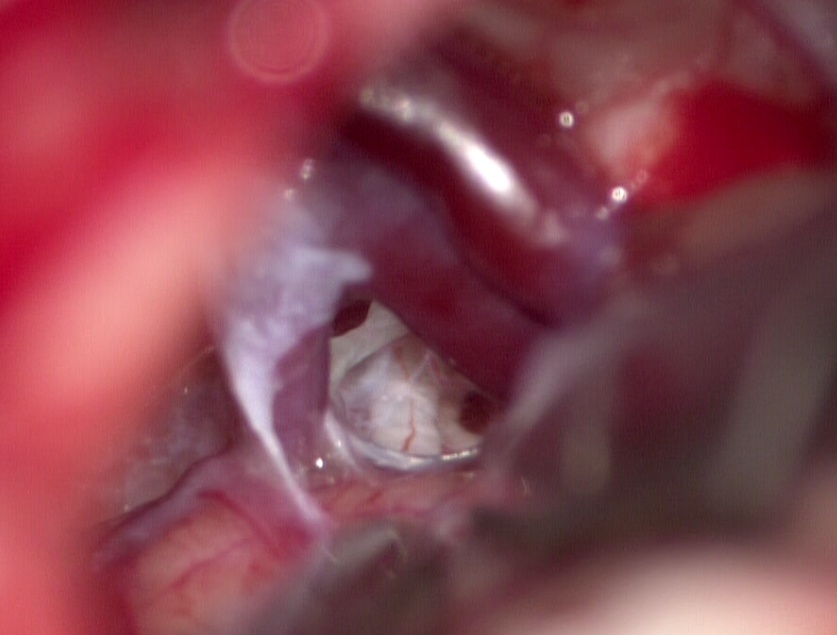

Технически операция выглядит следующим образом. Делается небольшой разрез в заушной области на стороне поражения. Проводится мини-краниотомия, или трепанация. Тканесберегающая, максимальными размерами до двух сантиметров. Осуществляется подход к структурам мостомозжечкового угла под микроскопом. Врач видит сосуд, чаще всего артериальный. Видит зону нейроваскулярного конфликта. Разъединяет спайки, укладывает специальный инертный материал и устраняет компрессию.